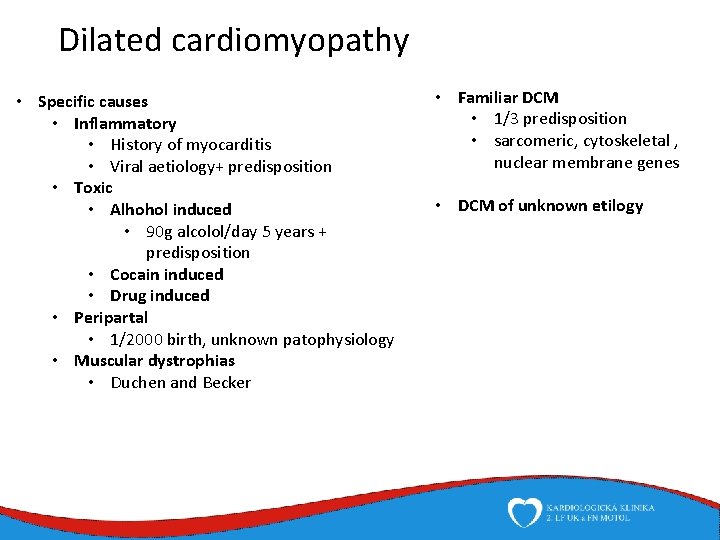

Dilated cardiomyopathy • Specific causes • Inflammatory • History of myocarditis • Viral aetiology+ predisposition • Toxic • Alhohol induced • 90 g alcolol/day 5 years + predisposition • Cocain induced • Drug induced • Peripartal • 1/2000 birth, unknown patophysiology • Muscular dystrophias • Duchen and Becker • Familiar DCM • 1/3 predisposition • sarcomeric, cytoskeletal , nuclear membrane genes • DCM of unknown etilogy